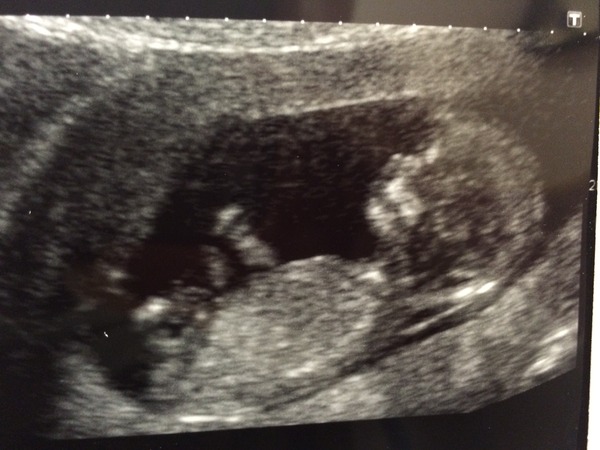

Everything is fine, scan went on for ages because baby was upside down with it's hands in the air Hmm having an absolute rave in there!

And they've moved my due date again to the 4th, so I'm 13 weeks on the nose today, skipped my whole 12th week this week

Anyhoo here is the little troublemaker once it finally decided to lay properly ...

Aww what a great picture BlueBananas! Very clear. Congratulations.

Obviously lots of us have naughty babies...one literally did a rolly polly whilst we were looking at him/her.

Great scan photo!

Blue beauliful scan picture Smile.

Yay Jucy lovely pic!

Look at your baby all stretched out & co-operative, the scanner kept huffing today because mine wouldn't take it's chin off it's chest

blue and jucy love your pics!

Lovely pics blue & jucy